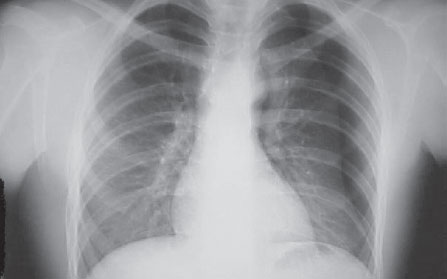

Radiografia de tórax em PA evidenciando de tórax em PA evidenciando pneumotórax à esquerda